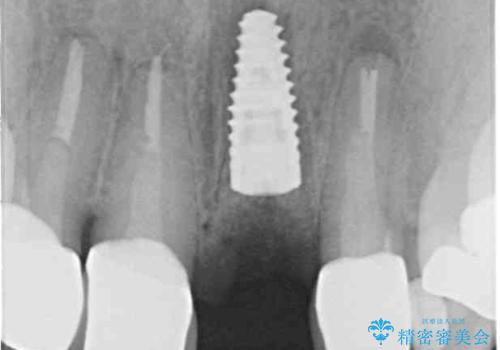

2. 折れてしまった前歯 インプラントによる補綴治療の治療中